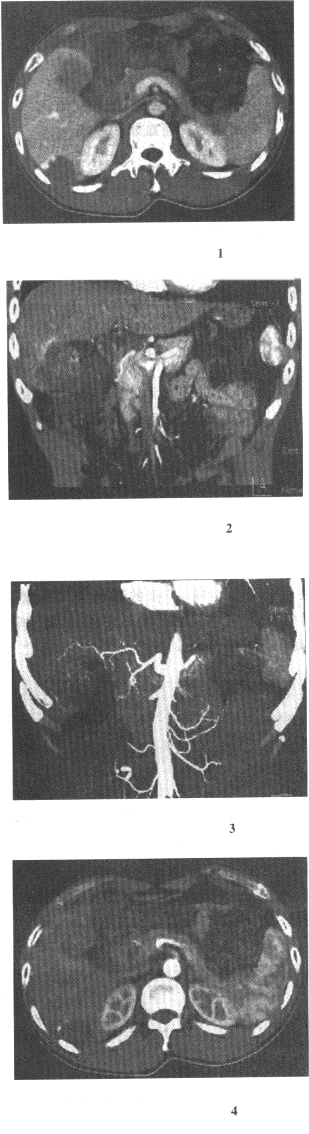

11.男,40歲,半年前因雙下肢麻木、發涼、疼痛于外院診斷血栓閉塞性脈管炎,近1周腹痛、腹脹,以中下腹為著,呈陣發性加劇就診,行CT增強掃描,如圖所示,下列描述正確的是

正確答案:ABCE 解題思路:ABCE均符合圖像改變,考慮為門靜脈及腸系膜內血栓形成。